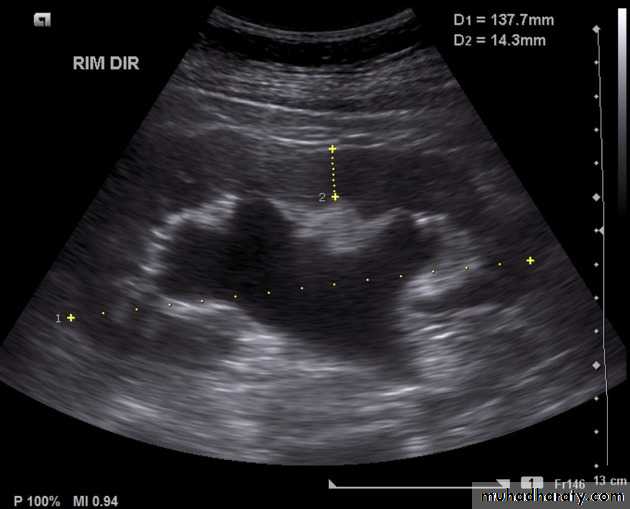

Renal ultrasound

• US is the 1st line investigation.Normal renal ultrasound shows:

• Smooth renal outlines• Renal parenchyma is of homogenous echoes that is similar or less reflective than the adjacent liver or spleen.

• Renal parenchymal surround the central echo complex.

• PCS and ureters are normally not visible